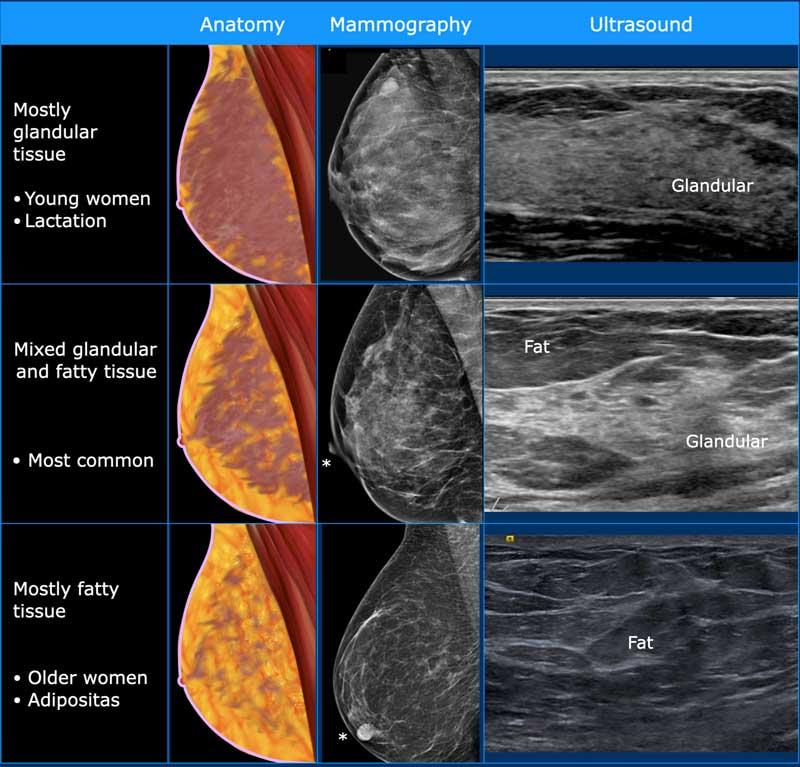

Siêu âm cho phép xác định thành phần mô vú: mô xơ tuyến đồng nhất – mô không đồng nhất – hoặc mô mỡ đồng nhất (hình).

Lưu ý rằng hình ảnh nhũ ảnh và siêu âm rất tương đồng nhau.

Ở phụ nữ trẻ, vú chủ yếu chứa mô tuyến.

Mô tuyến này có thể rất phát triển trong thời kỳ mang thai và cho con bú, đồng thời có thể biến đổi theo chu kỳ ở phụ nữ tiền mãn kinh, khiến vú có cảm giác u cục hoặc đau.

Ở phụ nữ lớn tuổi, mô tuyến dần được thay thế bởi mô mỡ, mặc dù một số phụ nữ lớn tuổi vẫn có thể còn một lượng mô tuyến đáng kể.

Ở phụ nữ béo phì, lượng mỡ trong vú nhiều hơn ngay cả ở độ tuổi trẻ hơn.